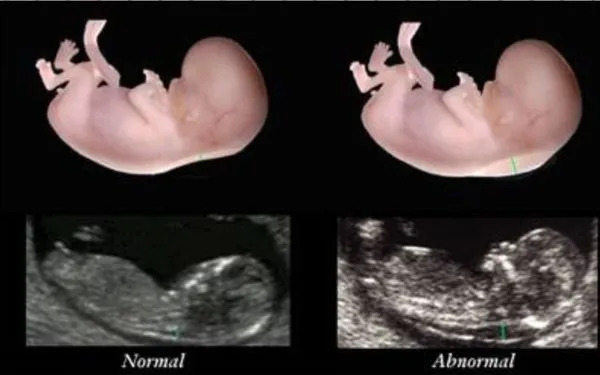

Nếp gấp da gáy (nuchal translucency) là một lớp dịch tích tụ ở phía sau cổ của thai nhi. Đo nếp gấp da gáy là một phần của xét nghiệm siêu âm thai kỳ, thường được thực hiện trong thai kỳ. Kết quả của đo nếp gấp da gáy có thể giúp phát hiện các dấu hiệu bất thường về nhiễm sắc thể hoặc các dị tật bẩm sinh ở thai nhi.

Đo nếp gấp da gáy là một trong những phương pháp sàng lọc quan trọng giúp phát hiện sớm nguy cơ của một số tình trạng nhiễm sắc thể, chẳng hạn như hội chứng Down (trisomy 21), hội chứng Edwards (trisomy 18), và hội chứng Patau (trisomy 13).

Các nghiên cứu đã chỉ ra rằng một nếp gấp da gáy dày hơn bình thường có thể liên quan đến các vấn đề sức khỏe nghiêm trọng ở thai nhi, bao gồm các vấn đề về tim mạch và các dị tật khác. Tuy nhiên, cần lưu ý rằng đo nếp gấp da gáy chỉ là một phần của quy trình sàng lọc và không phải là một xét nghiệm chẩn đoán.

Khi đo nếp gấp da gáy của thai nhi, chỉ số được coi là bình thường nếu nằm dưới 3,5mm và chiều dài của thai nhi từ 45mm đến 84mm. Chỉ số này giúp bác sĩ đánh giá nguy cơ mắc các bất thường nhiễm sắc thể của thai nhi.

Khi chỉ số nếp gấp da gáy thấp hơn 3,5mm, nguy cơ mắc hội chứng Down của thai nhi rất thấp. Đặc biệt, khoảng 90% thai nhi có chỉ số từ 2,5mm đến 3,5mm thường không mắc hội chứng này, cho thấy chỉ số nếp gấp da gáy là một dấu hiệu khá chính xác trong việc sàng lọc ban đầu.

Tuy nhiên, nếu chỉ số nếp gấp da gáy vượt quá giới hạn bình thường, nguy cơ mắc hội chứng Down và các bất thường nhiễm sắc thể khác tăng lên đáng kể. Ví dụ, khi chỉ số nếp gấp da gáy đạt mức 6mm, nguy cơ mắc các vấn đề về nhiễm sắc thể và tim mạch là rất cao, dù chỉ số này rất hiếm gặp.